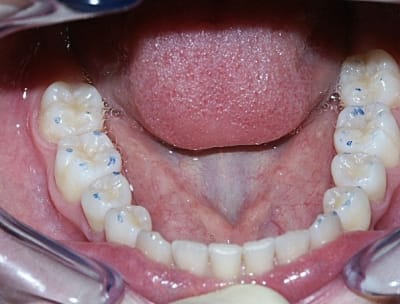

Avec l'arrivée des photos des moulages initiaux, je me suis dit" est ce le même cas", car:

avec la présentation du sujet (debut novembre)on parlait de classe III avec menton en galoche et en fait il semble qu'il y avait une grosse supra avec belle déviation à gauche et inversé d'articulé gauche.

La maman avait surement flashé sur le menton qui devait bien ressortir à cause du pli sous la lèvre inf.

Le trt ortho a du ramener la mand vers la droite mais comme le max n'est pas assez large la branche montante D remonte en Ar et le condyle vient compresser sa zone de réception.Il me semble donc qu'il faille bien augmenter la dimension transversale du max et la dv surtout à droite pour bloquer ce condyle droit dans sa course.J'avoue que c'est complexe mais elle ne doit pas être bien (cf photos),alors il faut faire qq chose.

bon je vous laisse encore quelques photos pour que vous puissiez argumenter la discussion.

Sinon, j'aimerai bien que quelqu'un me donne un vrai plan de traitement pour la patiente et la chronologie des thérapeutiques. Merci.

- Modèles : très belle supraclusion antérieure et infragnatie organiques latérales. Donc, très belle DSD magistrale et ou il ne reste plus qu'à appliquer ce qui est écrit supra.